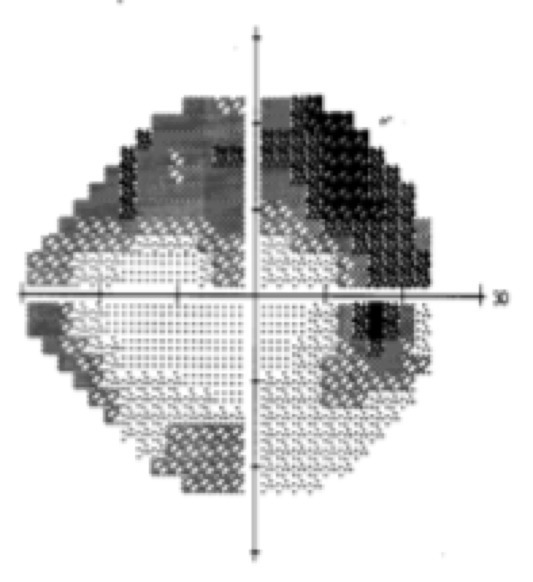

Rougeur en secteur dans l’épisclérite

Test à la fluorescéine négatif

Pas d’hypertonie oculaire